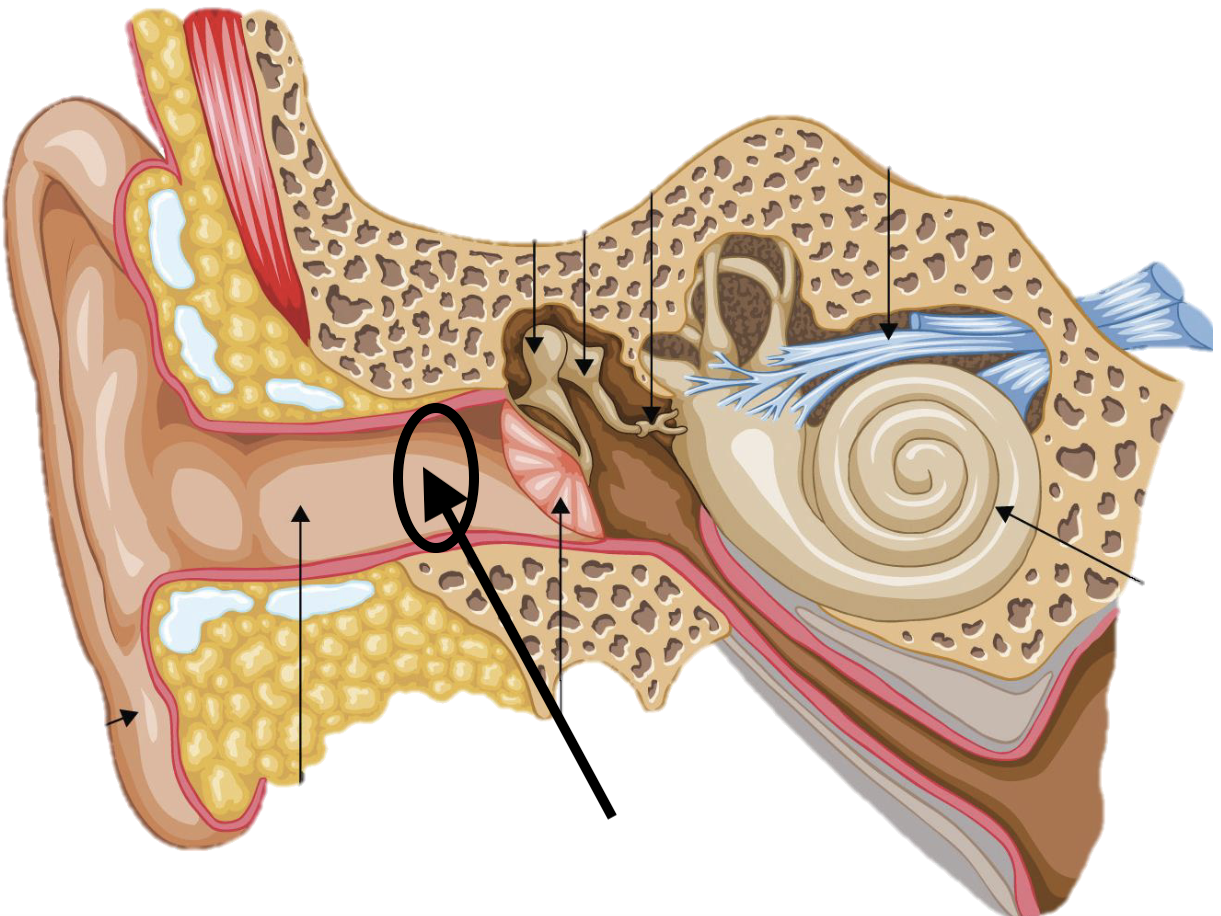

Name the feature of the ear ossicle

External acoustic meatus

Name the feature of the ear ossicle

Malleus

Name the feature of the ear ossicle

Incus

Name the feature of the ear ossicle

Stapes

Name the feature of the ear ossicle

Internal acoustic meatus

Name the feature of the ear ossicle

Cochlea

Name the feature of the ear ossicle

Temporal bone